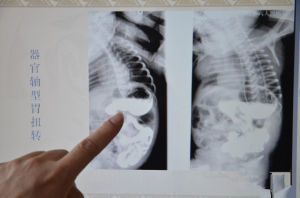

(1)X線鋇餐造影X線檢查是確診胃扭轉的首選方法。器官軸型胃扭轉的X線表現為:胃體和胃竇的胃大彎位置升高,致使胃大彎翻轉向上、胃小彎翻轉向下,形成一凸面向上、凹面向下的胃形,狀如蜷蝦;食管膈下段延長;食管與胃體黏膜皺襞交叉,胃黏膜呈螺鏇狀;胃內可見雙胃泡和雙液氣平面。網膜軸型胃扭轉表現為:胃竇部翻至左側並抬高,致使胃大彎翻向右,胃小彎翻向左;胃黏膜皺襞呈十字交叉,整個胃呈“蜷曲狀。混合型胃扭轉則兼有上述二型之特點。